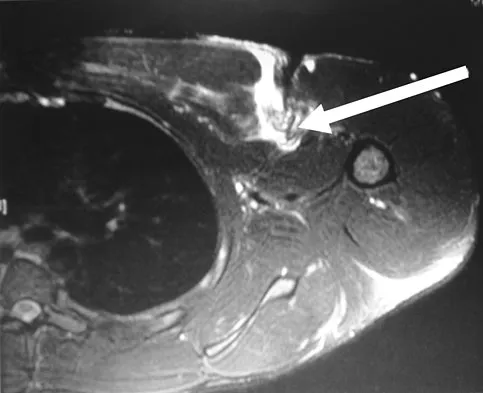

A 38-year-old left hand-dominant bodybuilder reports ecchymosis in the left axilla and anterior brachium after sustaining an injury while bench pressing 3 weeks ago. Coronal and axial MRI scans are shown in Figures 16a and 16b. What treatment method yields the best long-term results?

Explanation